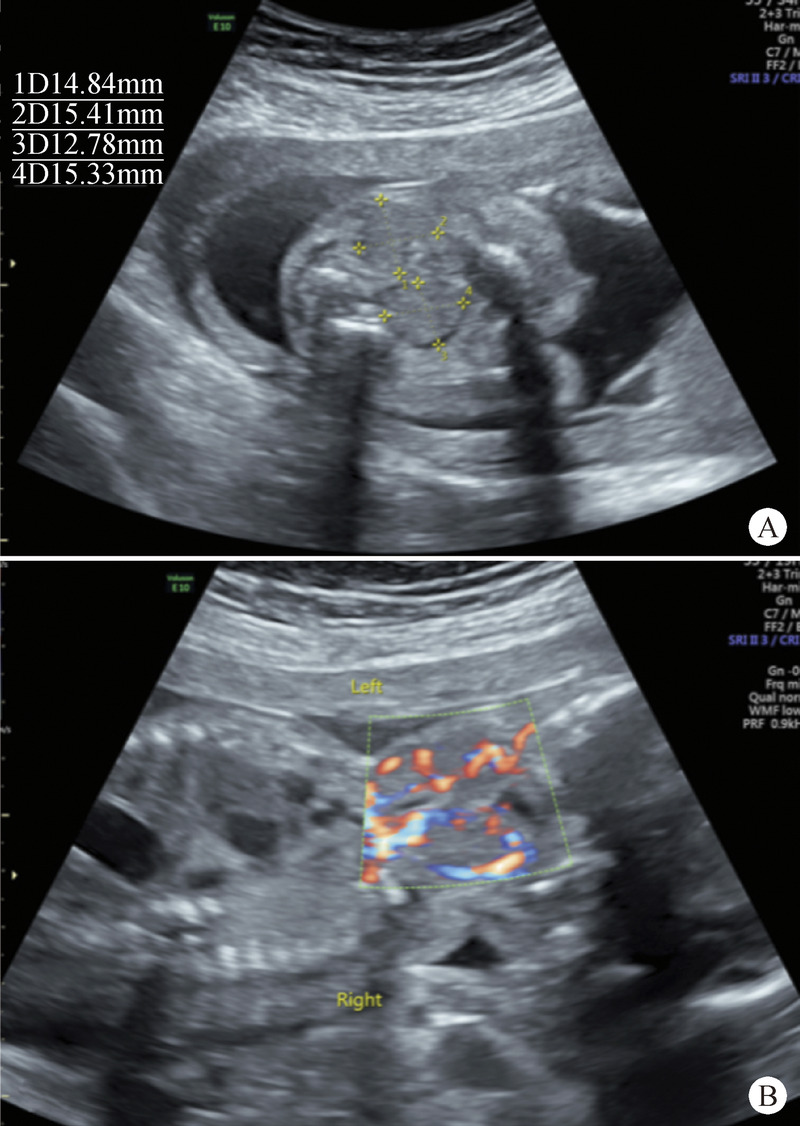

With the advances in fetal medicine, there will be more cases of congenital hypothyroidism (CH) diagnosed in the fetal period. However, there is no consensus on the management protocol. We present a successful case of conservatively managed fetal goitrous hypothyroidism due to compound heterozygous TG mutations. Goiter was observed in a fetus at 23 weeks of gestation. Because there was no evidence of transplacental passage of antithyroid antibody and drugs, iodine overload, and iodine deficiency, the fetus was highly suspected to have CH. Considering the potential risks of amniocentesis/cordocentesis, and lack of available parenteral levothyroxine in China, the fetus was closely monitored thereafter. A male neonate was delivered vaginally without complications at 39 weeks of gestation. We verified severe hypothyroidism in the infant and immediately initiated levothyroxine therapy. His growth and mental development were normal at the age of 8 month. Whole-exome sequencing showed that the neonate had two compound heterozygous mutations in the TG gene. We also performed a literature review of the prognosis of postnatal treatment of CH due to TG mutations and the result showed that postnatal treatment of CH due to TG mutations has a favorable prognosis. However, further prospective studies are warranted to verify this conclusion.

Abstract Image